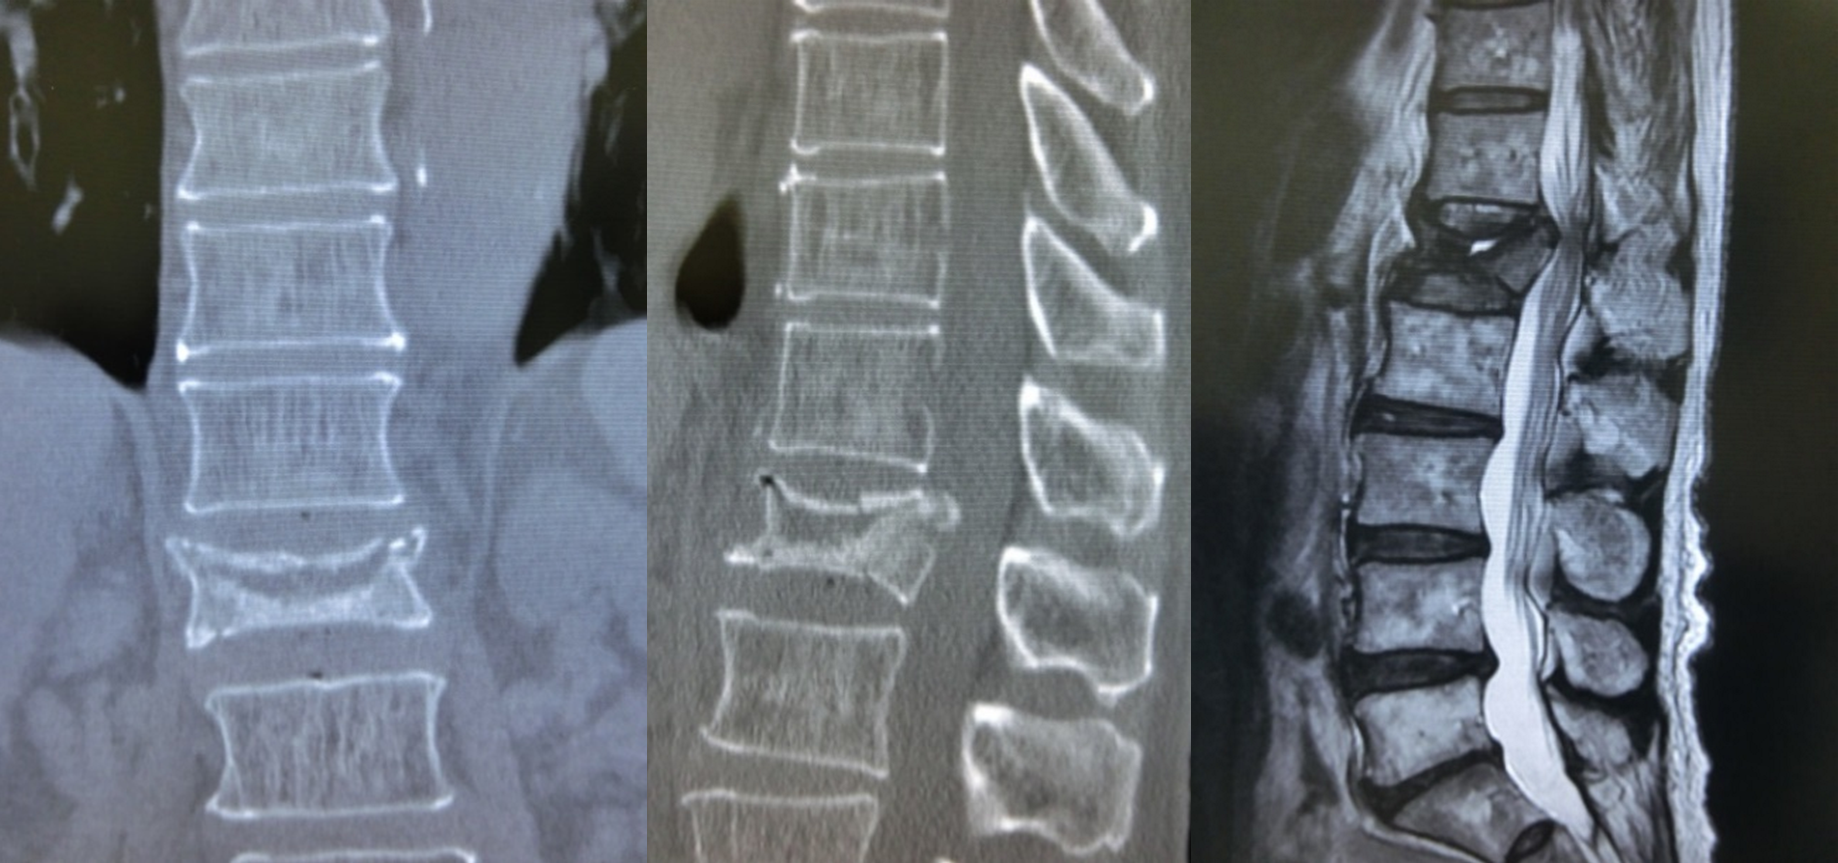

骨は加齢とともに強度が弱くなっていきます。特に、閉経後の女性はホルモンの変化により骨粗鬆症に至ることも少なくなく、軽い動作だけでも脊椎(せぼね)が骨折してしまうことがあります。こういった骨折を骨脆弱性(こつぜいじゃくせい)骨折と言い、脊椎の骨折は圧迫骨折とも言われます。初期にはレントゲンではっきりとした所見がないことがあり、より精密なMRI検査ではじめて診断されるケースもあります。

多くはコルセットなどの保存療法が選択され、つぶれた骨が3ヵ月程度で治癒して次第に痛みも改善します。しかしながら、数ヵ月経過しても骨折が治癒せず(偽関節と言います)、強い痛みが持続する場合には、手術治療が考慮されます。また、つぶれた骨が脊髄や馬尾神経などを圧迫して、下肢の痛みや麻痺、膀胱直腸障害などをきたし、重篤な神経障害が残る可能性が高いと判断された場合には、早急な手術治療が選択されることもあります。低侵襲な治療法として、つぶれた骨にセメントや人工骨を補填する椎体形成術という方法があります。骨折のタイプによっては、椎体形成術だけでは不十分な場合もあり、人工スペーサーや金属性のスクリューなどで脊椎を固定し安定化させる方法もあります。一般にご高齢の方や、内科的な併存疾患をお持ちの方も多いため、 手術には各診療科と協力して様々な工夫と準備が必要になります。また、一度圧迫骨折を起こすと、その後も同様の骨折を繰り返すことがあるため、手術後も継続的な骨粗鬆症の治療を行うことが重要です。

脊椎圧迫(破裂)骨折・骨粗鬆症性椎体骨折の最小侵襲手術として、BKP、VBS、最小侵襲脊椎安定術などの手術方法があります。